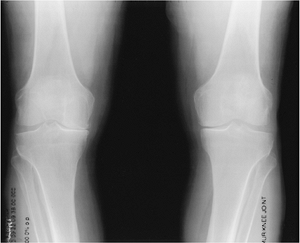

FIGURE 13-12 Standing views of the knees showing typical asymmetric medial compartment narrowing.